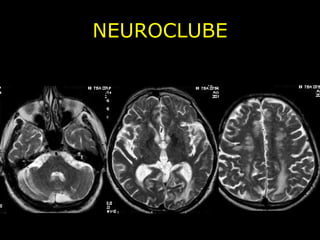

NEUROCLUBE CASO 1

NEUROCLUBE